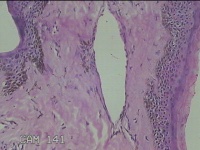

头部新生物

性别

男

年龄

31岁

临床诊断

纤维瘤

一般病史

头部皮肤起新生物1年。

标本名称

大体所见

灰白粉红色新生物1.7x0.5x0.3cm一个,表面糜烂,肿物表面有大量毛发。